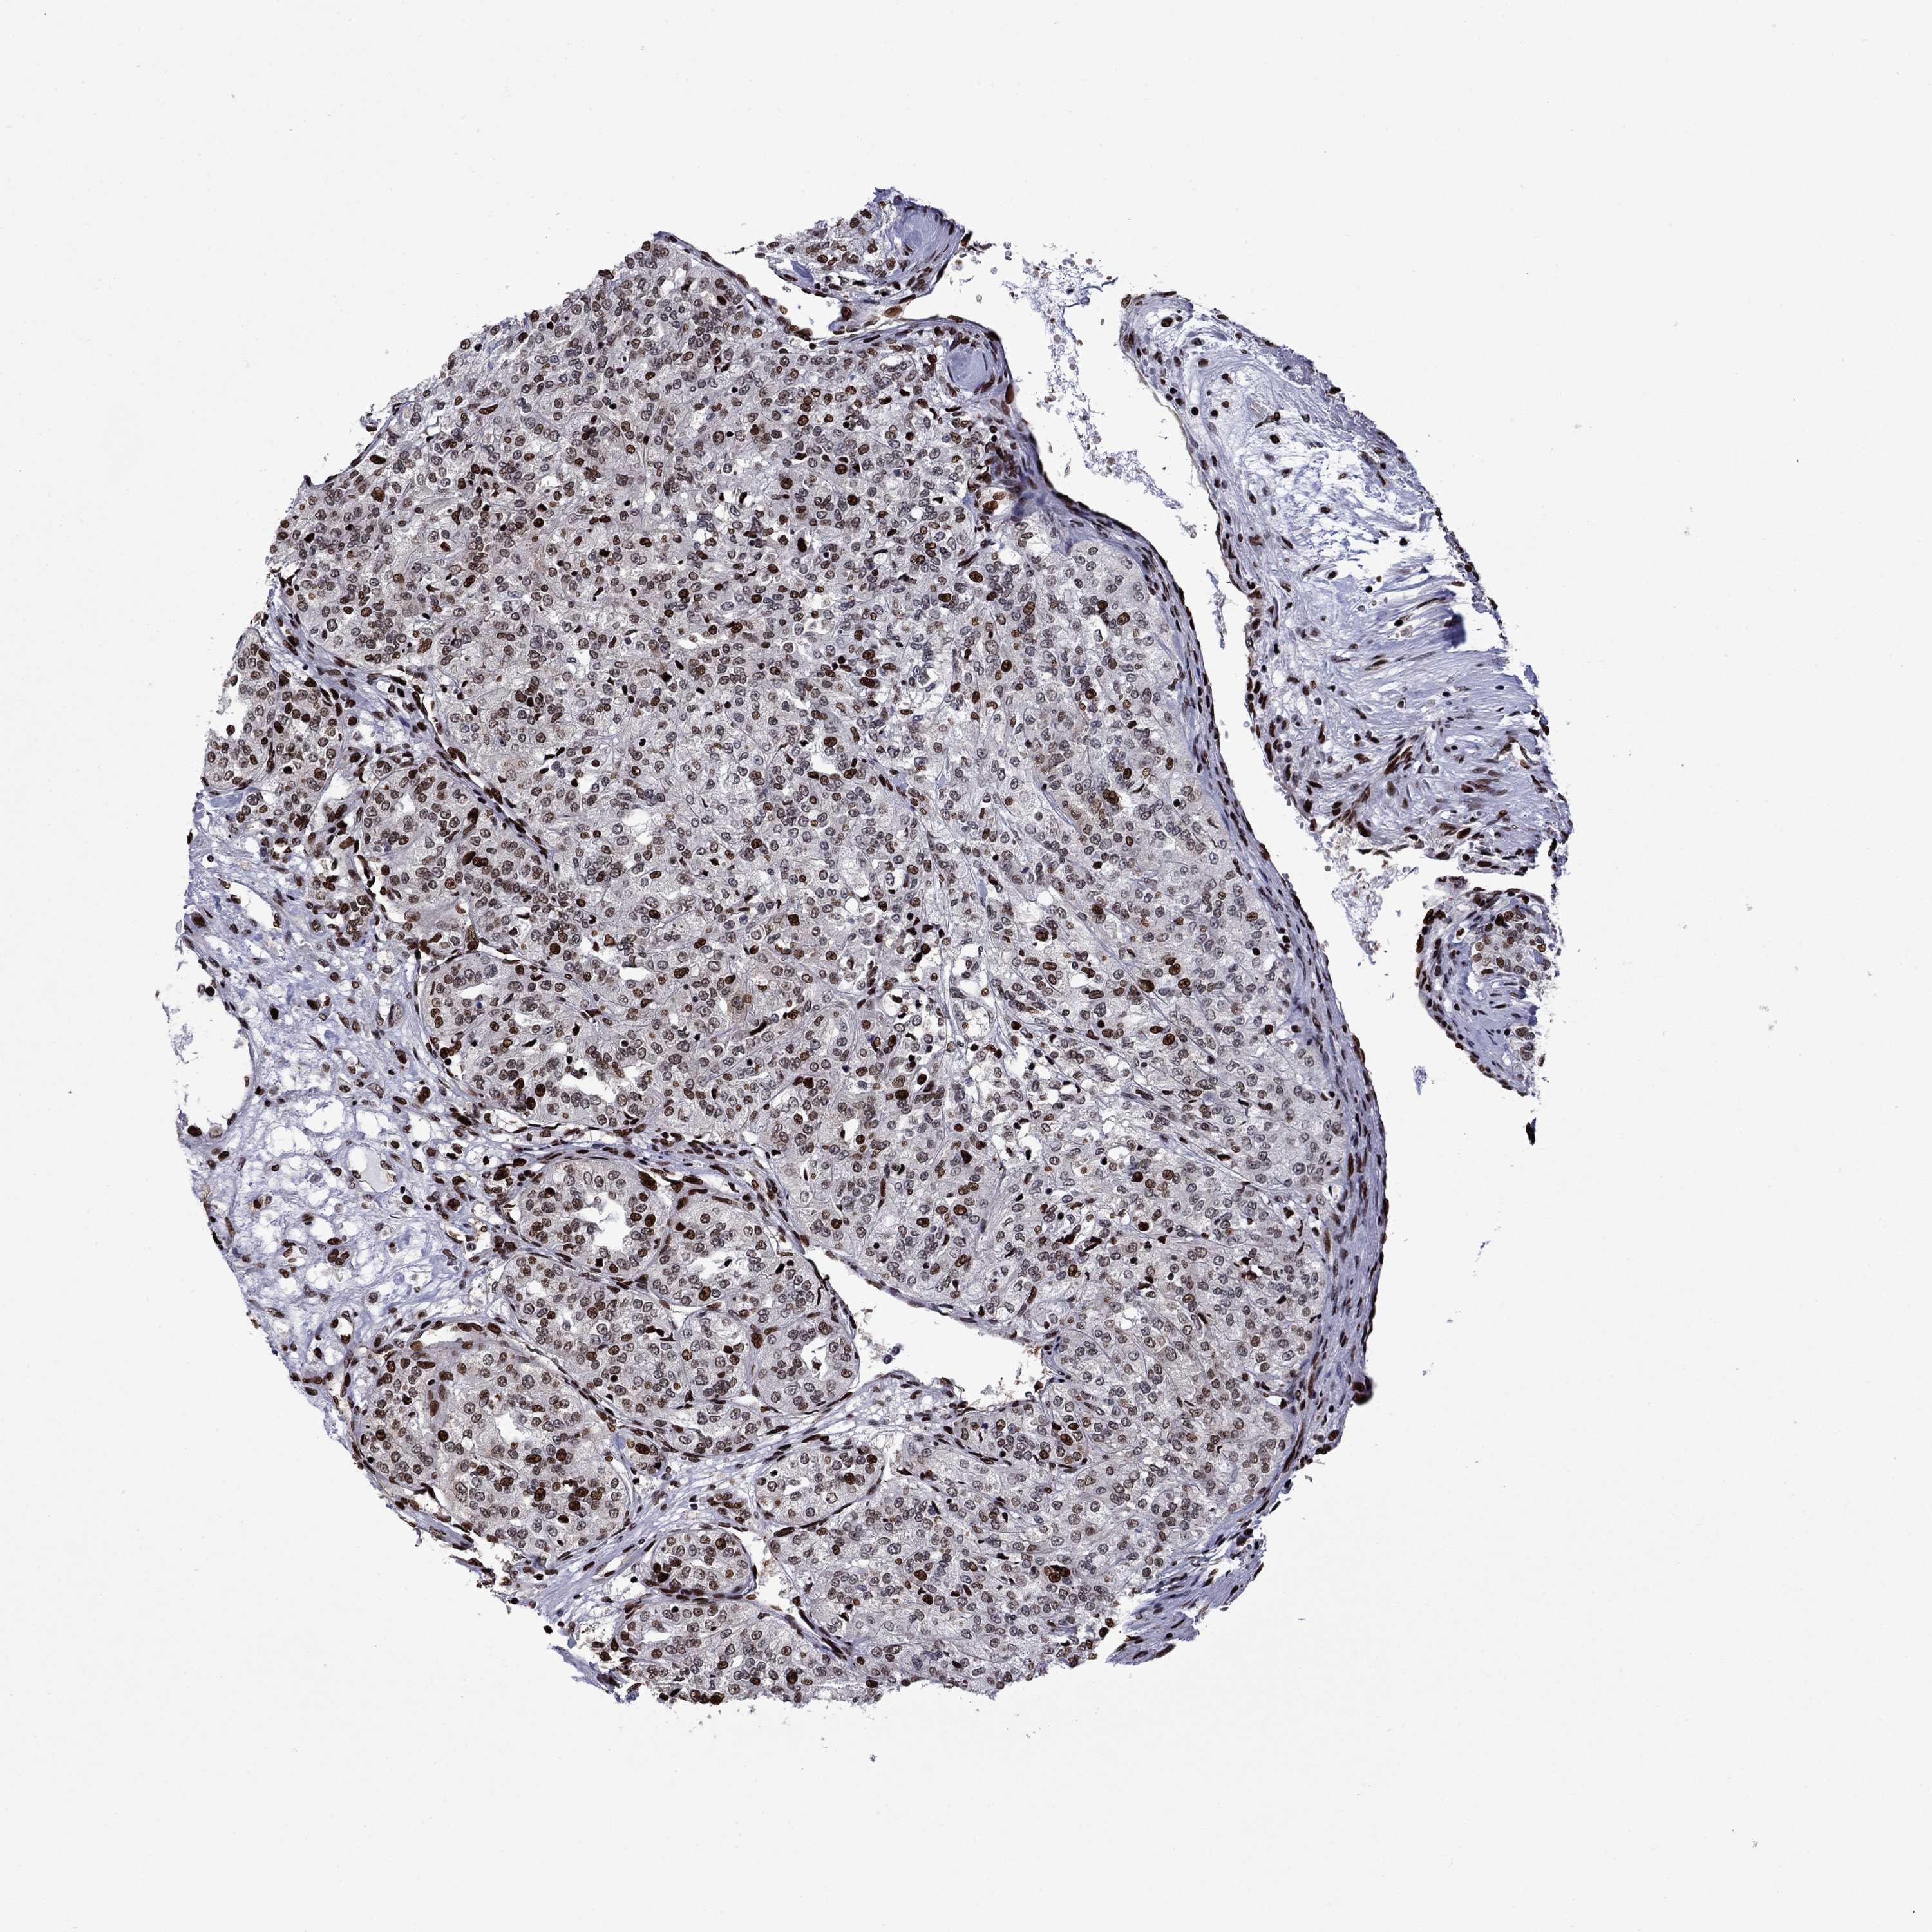

KIDNEY RENAL CLEAR CELL CARCINOMA (VALIDATION) - Interactive survival scatter ploti

The Survival Scatter plot shows the clinical status (i.e. dead or alive) for all individuals in the patient cohort, based on the same data that underlies the corresponding Kaplan-Meier plots. Patients that are alive at last time for follow-up are shown in blue and patients who have died during the study are shown in red.

The x-axis shows the expression levels (FPKM) of the investigated gene in the tumor tissue at the time of diagnosis. The y-axis shows the follow-up time after diagnosis (years). Both axes are complimented with kernel density curves demonstrating the data density over the axes. The top density plot shows the expression levels (FPKM) distribution among dead (red) and alive patients (blue). The right density plot shows the data density of the survived years of dead patients with high and low expression levels respectively, stratified using the cutoff indicated by the vertical dashed line through the Survival Scatter plot. This cutoff is automatically defined based on the FPKM cutoff that minimizes the p-score. The cutoff can be changed by dragging the vertical line or by entering a cutoff value in the square labeled "Current cut-off".

Under the Survival Scatter plot the p-score landscape (black curve; left axis) is shown together with dead median separation (red curve; right axis). Dead median separation is the difference in median mRNA expression between patients who have died with high and low expression, respectively. It is calculated as follows: median FPKM expression of dead patients with high expression - median FPKM expression of dead patients with low expression. This is intended to aid the user in visually exploring custom cutoffs and the associated p-scores and dead median separation.

Individual patient data is displayed and can be filtered by clicking on one or more of the category buttons on the top of the page. Categories describing expression level and patient information include: high, low, alive, dead, female, male and tumor stages. The scale of the x-axis can be toggled between linear and log-scale by clicking on the "x log" button. Mouse-over function shows TCGA ID, patient information and mRNA expression (FPKM) for each patient.

& Survival analysisi

Kaplan-Meier plots summarize results from analysis of correlation between mRNA expression level and patient survival. Patients were divided based on level of expression into one of the two groups "low" (under cut off) or "high" (over cut off). X-axis shows time for survival (years) and y-axis shows the probability of survival, where 1.0 corresponds to 100 percent.

LIMK1 is not prognostic in Kidney Renal Clear Cell Carcinoma (validation)

Best expression cut offi

Based on the FPKM value of each gene, patients were classified into two groups and association between prognosis (survival) and gene expression (FPKM) was examined. The best expression cut-off refers the FPKM value that yields maximal difference with regard to survival between the two groups at the lowest log-rank P-value. Best expression cut-off was selected based on survival analysis .

When clicking on this number, the vertical dashed line indicating cut-off, the interactive survival plot, and the Kaplan-Meier curve will be adjusted to show results based on the best expression cut-off.

: 12.79

TCGA RNA samplesi

RNA-seq data is reported as average FPKM (number Fragments Per Kilobase of exon per Million reads), generated by the The Cancer Genome Atlas (TCGA) .

Normal distribution across the dataset is visualized with box plots, shown as median and 25th and 75th percentiles. Points are displayed as outliers if they are above or below 1.5 times the interquartile range. FPKM values of the individual samples are presented next to the box plot.

Average pTPM 21.1

Number of samples 100